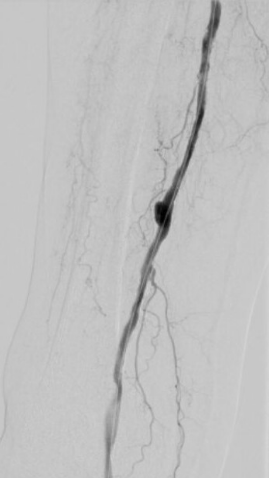

5. 选择6*60mm Shockwave冲击波球囊处理股腘动脉

本例患者股浅动脉重度闭塞,股浅远端重度钙化病变近收肌管,利用Shockwave冲击波球囊获得满意的管腔准备后联合使用DES,为保障远期通畅植入支架,支架膨胀形态理想。

我国患者股浅动脉又多以长段闭塞病变为主,为保障远期通畅率,支架的植入往往不可避免,此时如何优化支架膨胀则至关重要。利用“聚焦式”的冲击波能量作用于重度钙化环最薄弱处,在低压下安全打开钙化斑块,尤其是限制血管床弹性的环形钙化,可有效增加管腔顺应性,减少弹性回缩。